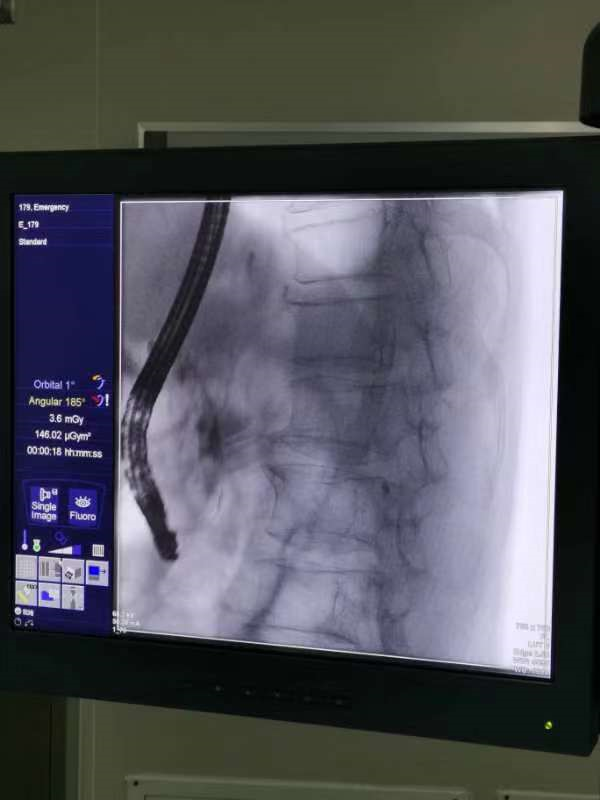

术中所见

取石篮是什么小小结石  “胆”敢来犯——记平湖二院又一例ERCP微创胆道取石术_https://www.jmylbn.com_新闻资讯_第1张

造影→乳头切开→网篮取石→鼻胆管引流